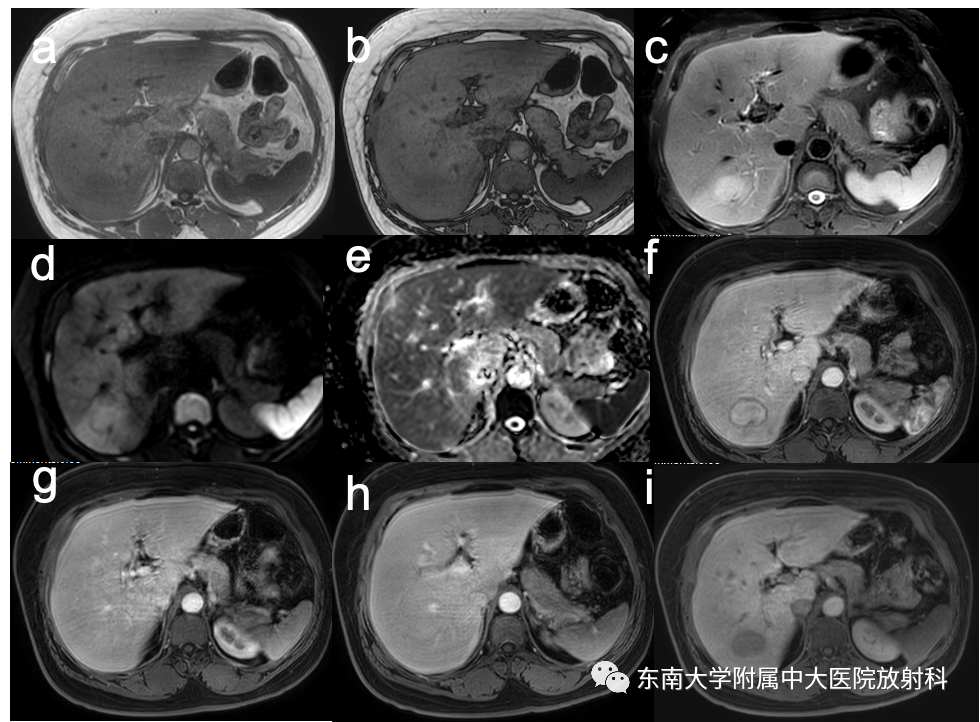

【PPT】肝细胞腺瘤

病史

女,47岁

主诉:右上腹不适2月

否认“高血压”、“糖尿病”、“肝炎”病史